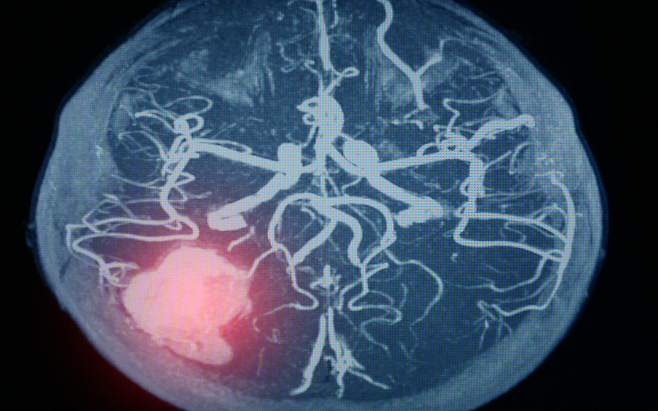

뇌출혈은 예고 없이 찾아오고, 한 번 겪으면 삶 전체를 송두리째 흔든다. 단 한 번의 출혈로 말이 어눌해지거나, 반신마비가 오기도 하고, 심할 경우 목숨까지 잃을 수 있다.

뇌출혈의 가장 큰 원인은 고혈압이다. 높은 혈압은 뇌혈관을 약하게 만들고, 결국 작은 충격에도 혈관이 터지게 한다. 혈압은 숫자가 아니라 생명줄이다. 하루 10분 걷기, 싱겁게 먹기, 충분한 수면, 스트레스 관리.

이 네 가지를 꾸준히만 해도 혈압은 안정된다. 특히 아침에 일어나기 전, 갑작스럽게 움직이기보다 몸을 천천히 일으키는 습관도 중요하다. 혈압이 급상승하는 순간이 뇌출혈 위험의 시간대다.